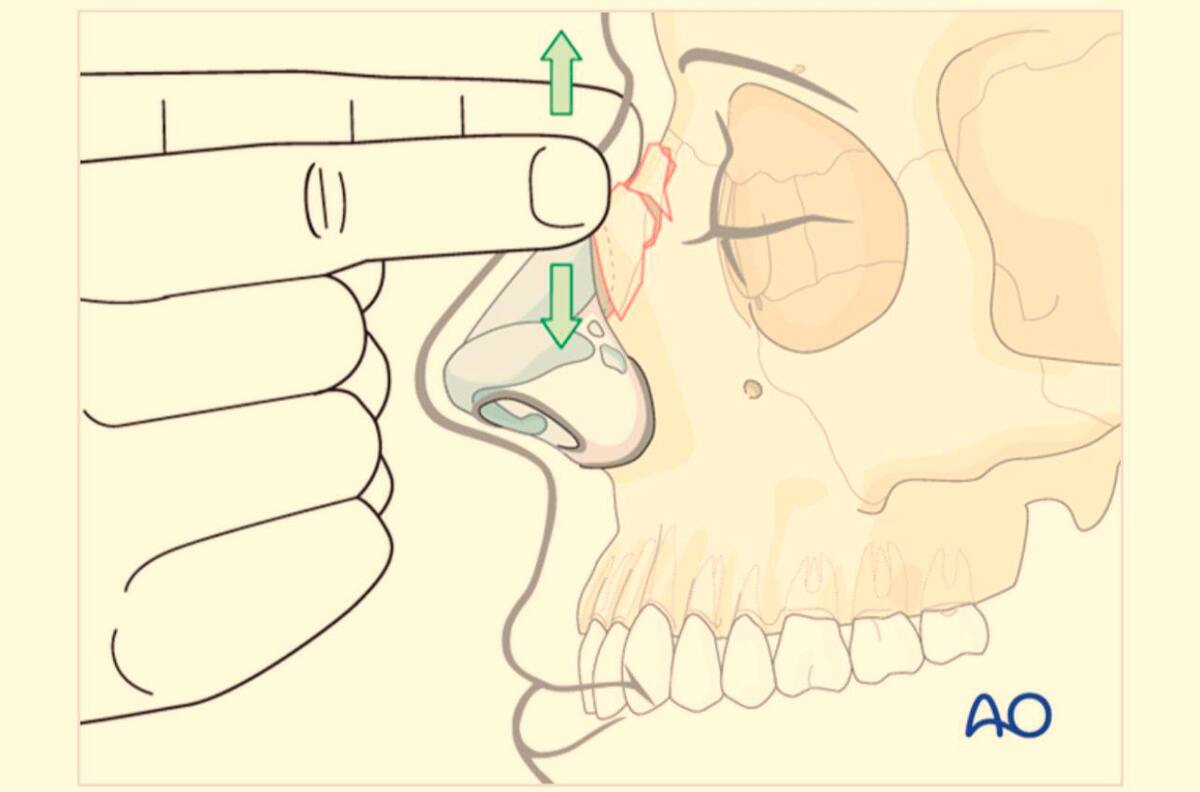

El estudio se llevó a cabo en dos etapas. En la primera etapa, los pacientes que consultaron el servicio de urgencias del hospital con fracturas nasales fueron diagnosticados clínicamente e imagenológicamente. Luego, con el consentimiento informado de los pacientes, se utilizó la escala internacionalmente reconocida “Nose Scale” o “escala Nose” para evaluar parámetros funcionales y se realizó una escala de evaluación subjetiva para medir la estética del paciente.

La segunda etapa de la evaluación se efectuó dos meses después del procedimiento de reducción cerrada de la fractura nasal. Los resultados de esta investigación buscan llenar un vacío en los datos estadísticos sobre el trauma facial en Colombia, y proporcionar un mejor entendimiento y tratamiento para los pacientes afectados.

La lógica detrás de la reducción cerrada de la fractura nasal implica la evaluación de parámetros utilizando las mismas escalas previamente mencionadas en ambas etapas. Finalmente, se realizó un análisis estadístico de los datos recolectados y se obtuvo una conclusión que permitió determinar que el procedimiento quirúrgico logró los resultados esperados tanto para el médico como para el paciente.